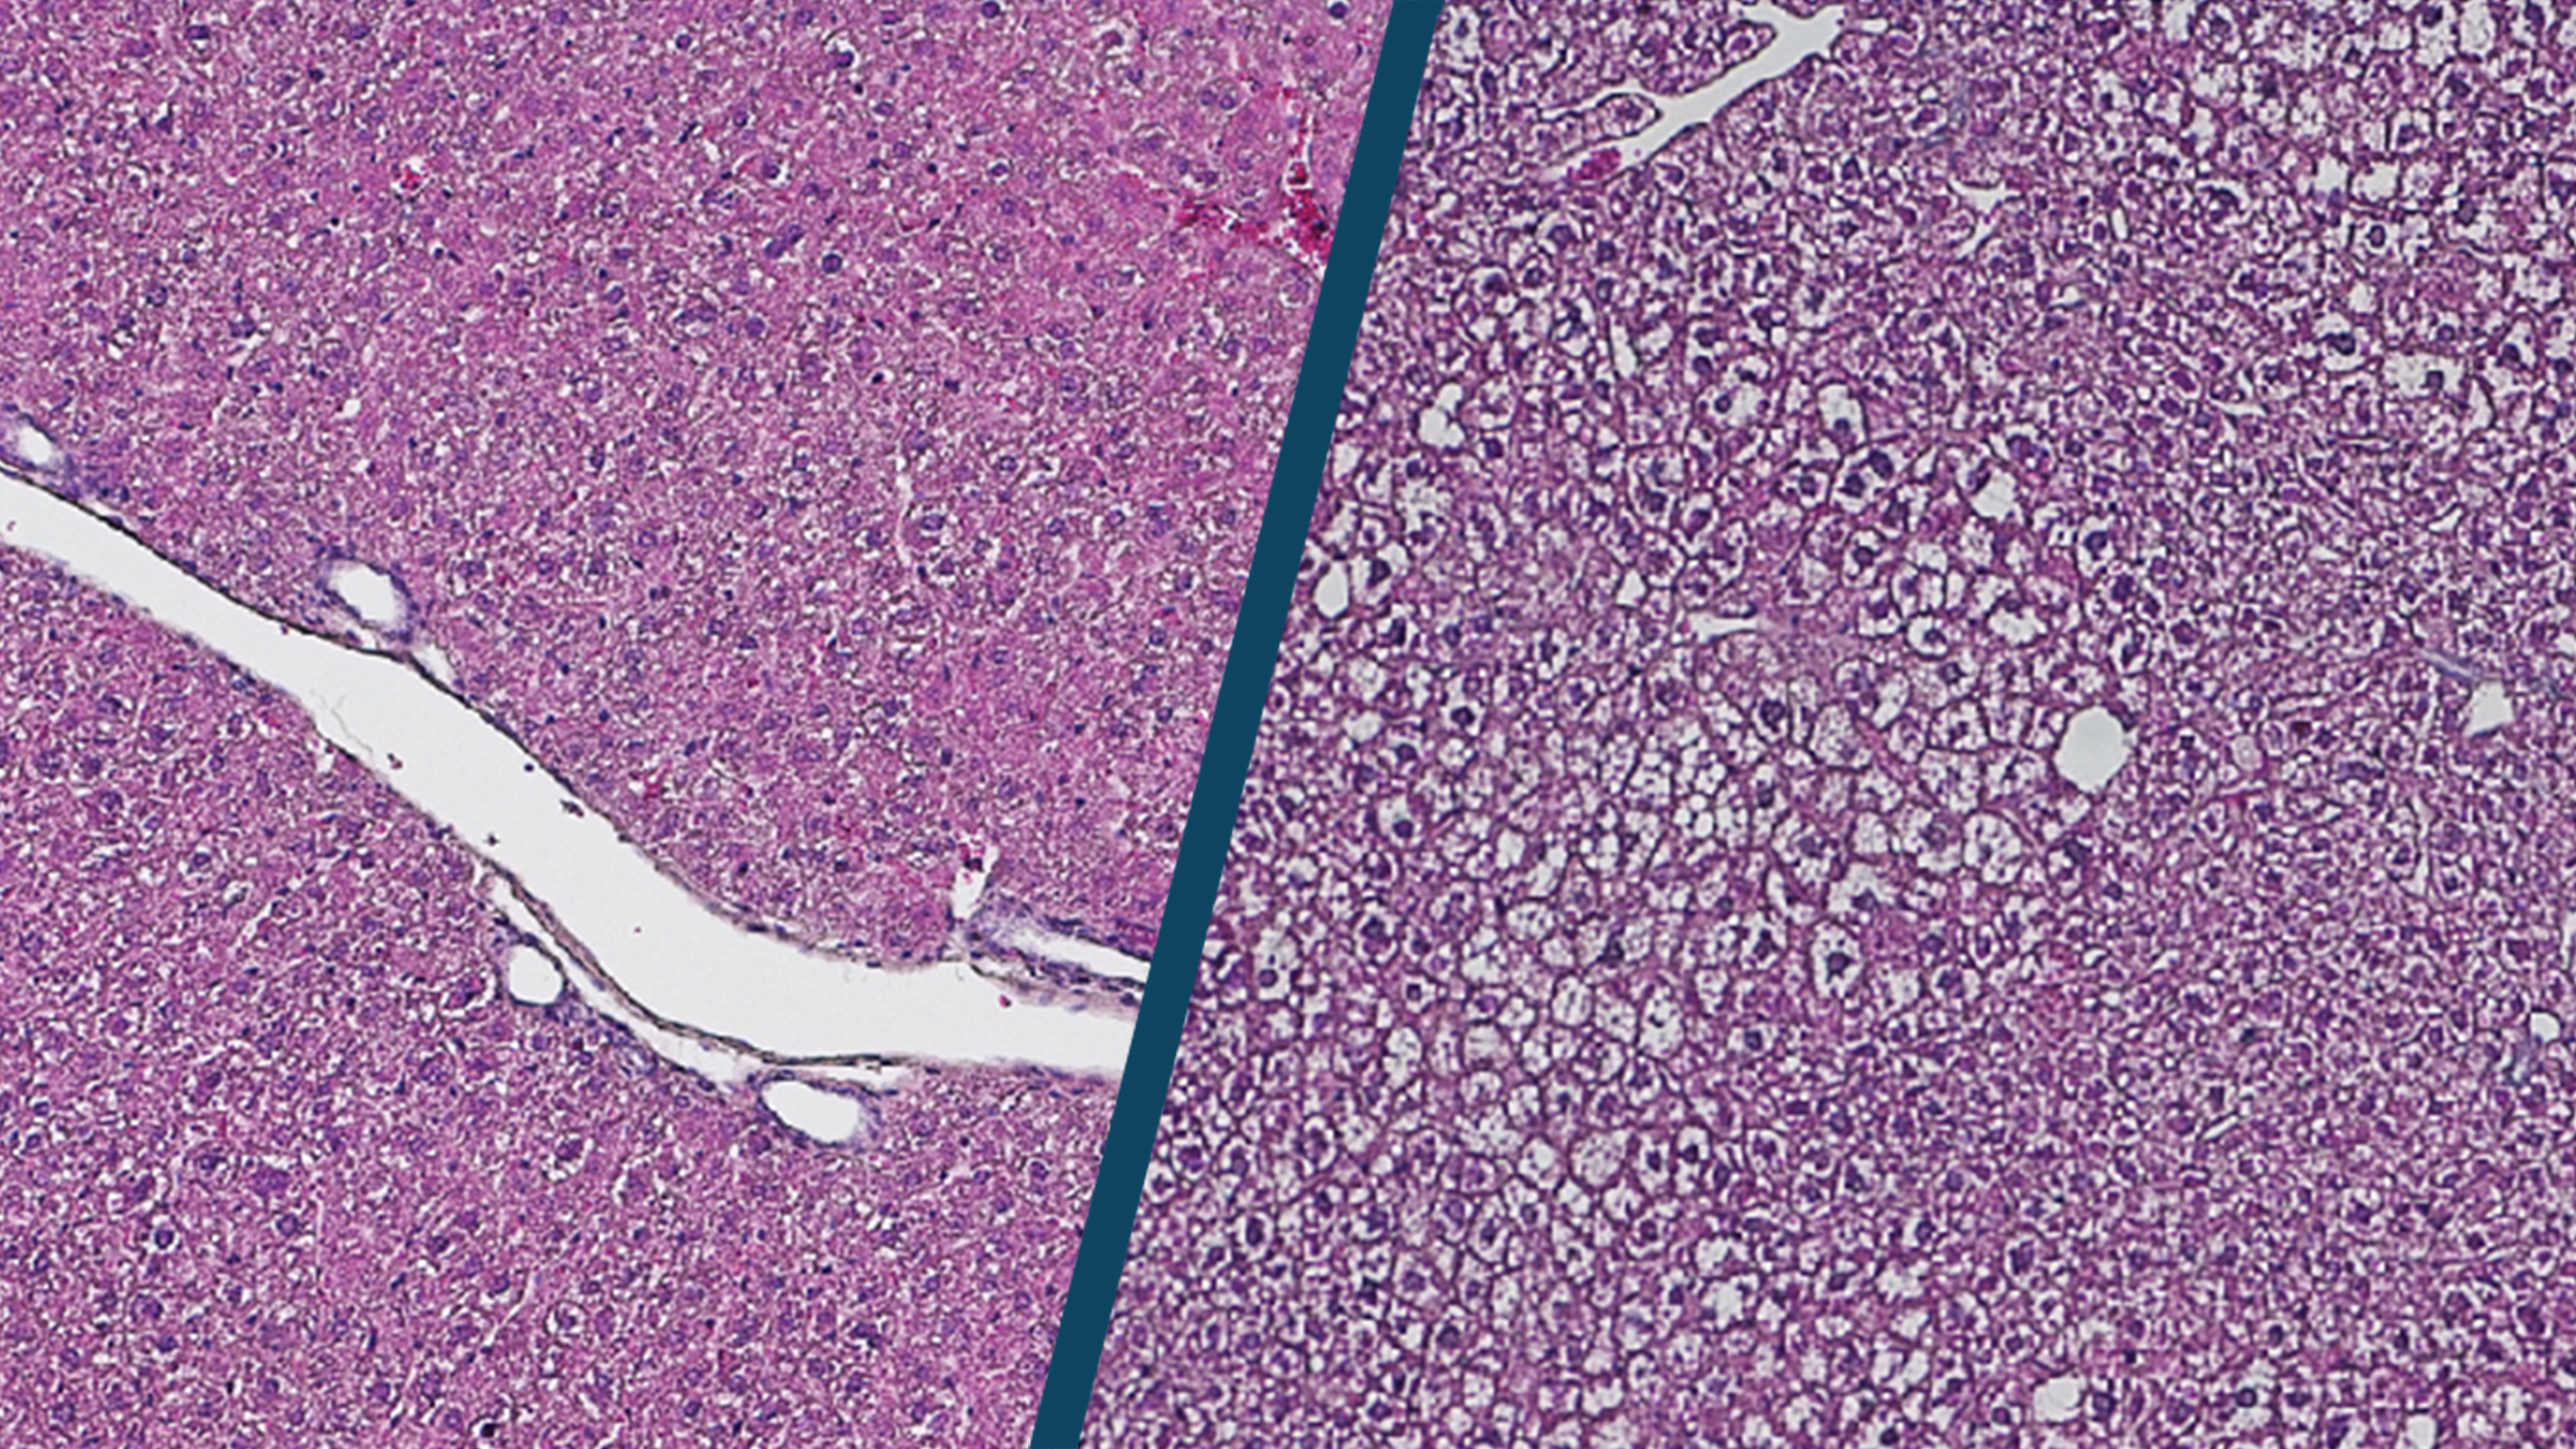

The liver can regenerate even in old age and remains surprisingly fit, even though the chromatin in its cells undergoes major remodeling due to epigenetic changes, as researchers from the Max Planck Institute for Biology of Ageing in Cologne have now discovered. One possible reason why the transformation has minor consequences could be a mechanism that the researchers now describe in the journal Molecular Systems Biology.

Changes in epigenetics are considered to be a cause of ageing processes. Epigenetics describes changes in genetic information that do not alter the sequence of the genes themselves, but influence their activity. Among other things, this can be regulated by the accessibility of proteins to DNA as part of chromatin. In this study, the researchers observed in liver cells that the DNA of liver cells becomes much less packaged with age. This makes the DNA more accessible to produce the messenger molecule RNA. "If the DNA is readily accessible, we should also see greater amounts of RNA made. But that was not the case at all," says Peter Tessarz, head of the study.